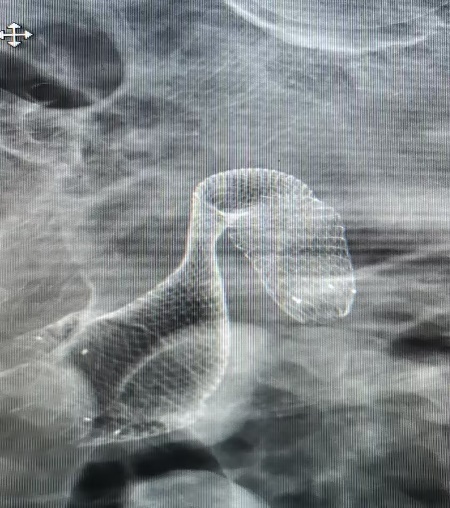

肠道支架置入术:通过内镜放置一个金属支架,将狭窄的肠道撑开,像在堵塞的隧道里架起一座“桥梁”,迅速解除梗阻,待病人情况稳定后,再择机进行后续治疗。这种方式创伤小、恢复快,但同样存在穿孔、出血等风险,且对操作医生技术要求极高。

架设“生命之桥”:在放置支架时,因肿瘤形态导致支架与肠壁形成了一个危险的30度夹角,难以越过狭窄段。此时若强行推进,极易导致肠道穿孔,后果不堪设想。

千钧一发之际,陈华沉着应对,通过反复、轻柔地推拉和调整,不断尝试最佳角度,如同在体内进行一场精密的“穿针引线”。最终,凭借丰富的经验和稳定的手法,支架被精准地放置到了预定位置,肠道瞬间被撑开,“生命通道”恢复了畅通!